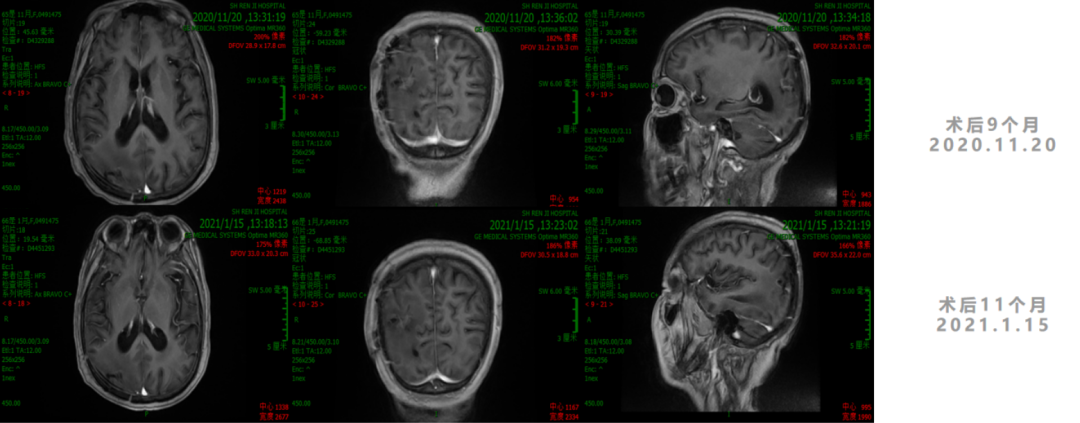

诊疗经过

2. 2020年7月1日起,行TTFields治疗+TMZ 6周期。

3. 2021年3月18日,2021年3月起,患者诉左侧肢体乏力,需搀扶行走。影像学检查显示,右侧脑室后角旁见结节样环形强化灶,直径7-8mm。MRS:NAA峰可见下降,Cho峰升高。Cho/Cr为0.748,Cho/NAA为2.13,考虑肿瘤复发可能。患者行射波刀治疗(24Gy/4FX),TMZ+安罗替尼2周期,TTFields重新定位,电场治疗调整贴片位置。